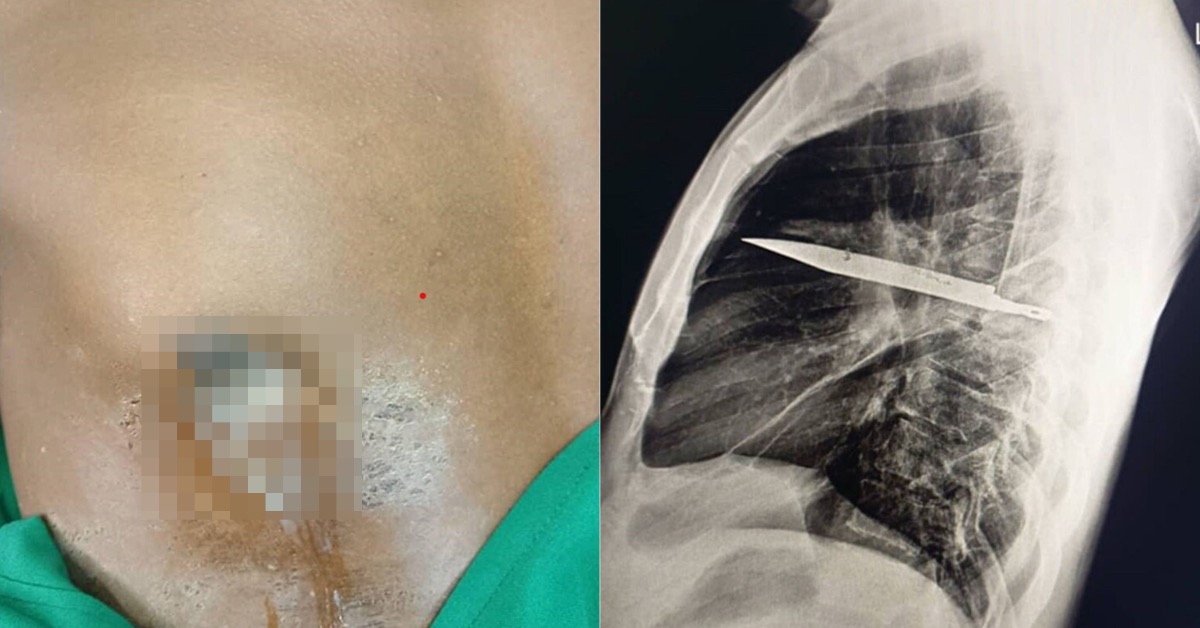

醫師隨即安排胸腔X光檢查。畫面清楚顯示,右肩胛骨位置有一片利刃狀「金屬殘留物」,從肩胛骨方向刺入胸腔,周圍被膿液與壞死組織包圍,顯示已存在相當長一段時間。

進一步評估後,醫師研判這片刀刃極可能是當年衝突時遺留在體內,時間約8年。之所以沒有立刻要命,是因為刀刃位置非常「剛好」,避開了心臟、大血管與主要肺部結構,才讓男子這麼多年來幾乎毫無異狀。